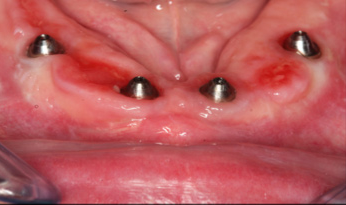

Figure 9 and Figure 10 demonstrate the technology that the dentist and dental laboratory can accomplish within one appointment after diagnostic evaluations, virtual setups, and engineering for provisionals and final restorations. For this patient, occlusion was developed in the laboratory and delivered on surgery day (Figure 11). After 4 months of postoperative healing (Figure 12), the gingival tissues displayed keratinized tissue around the multi-unit abutments. The positive soft-tissue response was consistent with osseointegration of the dental implants. The final restoration was verified with digital scans and analog impressions of the PMMA provisional to replicate the soft-tissue architecture and occlusion related to the opposing arch. A computer-aided and milled zirconia screw-retained full-arch mandibular restoration was implemented, characterized to meet the patient's and dentist's expectations (Figure 13). After screw retention and occlusal verification, a CBCT image was taken to verify final seating of the restoration and radiographic evaluation of the implants (Figure 14).

Fig 9. Bone-level guide.

Figure 9

Fig 10. Guided smile technology.

Figure 10

Fig 11. PMMA full-arch fixed provisional on the

day of surgery.

Figure 11

Fig 12. Keratinized gingiva 4 months postoperatively.

Figure 12